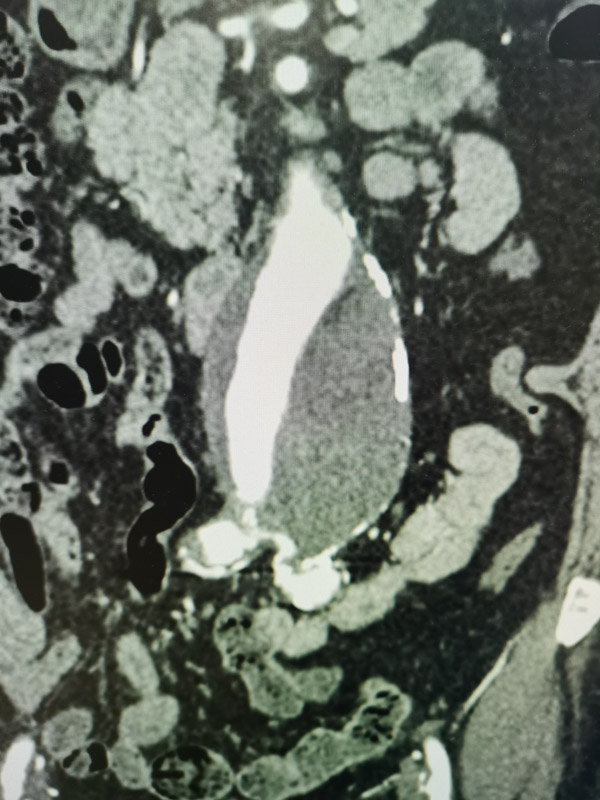

據(jù)我院心臟血管外科主任醫(yī)師陳俞宏介紹,腹主動(dòng)脈瘤就像個(gè)膨大的氣球,只不過里面是流動(dòng)的高壓血流。“氣球”在血流沖擊作用下越來越大,一旦破裂,就會(huì)發(fā)生致命性的大出血并在很短時(shí)間內(nèi)發(fā)生低血容量休克而導(dǎo)致死亡,十分兇險(xiǎn)。該患者的情況比較復(fù)雜,因腹主動(dòng)脈瘤瘤頸扭曲,入路狹窄閉塞,不適合介入支架治療,只能選擇開放手術(shù),且右髂外動(dòng)脈已經(jīng)完全閉塞,所以需要先開通髂動(dòng)脈血管,再將腹主動(dòng)脈瘤切除并置換人工血管。按照傳統(tǒng)的手術(shù)方案,需要分兩次手術(shù)進(jìn)行,一個(gè)手術(shù)做好后,要等患者恢復(fù)后才能實(shí)施第二次手術(shù)。為了減輕患者的痛苦,體現(xiàn)以病人為中心的理念,經(jīng)過多學(xué)科聯(lián)合診療討論,同意血管外科團(tuán)隊(duì)提出的復(fù)合手術(shù)方案。在實(shí)時(shí)影像學(xué)的引導(dǎo)下,采用介入技術(shù)與傳統(tǒng)外科技術(shù)聯(lián)合治療,使原本需要多次的手術(shù),一次就能搞定,患者無需在介入室和外科手術(shù)室之間多次轉(zhuǎn)移, 提高了手術(shù)效率,避免二次麻醉,節(jié)省了醫(yī)療費(fèi)用。

最終,血管外科團(tuán)隊(duì)在最新的復(fù)合手術(shù)室中為其施以右髂動(dòng)脈球囊血管成形術(shù)+右髂外動(dòng)脈支架置入術(shù),經(jīng)精確測(cè)量,將一枚金屬裸支架植入右髂動(dòng)脈開口處,術(shù)中造影復(fù)查發(fā)現(xiàn)右髂總動(dòng)脈、髂外動(dòng)脈恢復(fù)通暢。

隨后繼續(xù)進(jìn)行腹主動(dòng)脈瘤切除+人工血管置換術(shù),經(jīng)過三個(gè)多小時(shí),手術(shù)順利結(jié)束,術(shù)后患者在重癥監(jiān)護(hù)室觀察一個(gè)晚上,次日即轉(zhuǎn)回血管外科病房繼續(xù)治療。